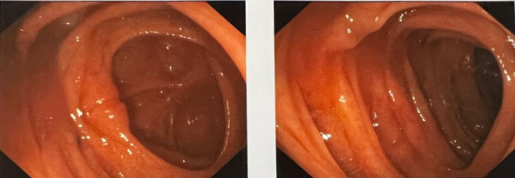

年过中旬的乔先生近30年来饱受大便习惯伴性状改变的困扰,大便不成形、稀,频次多、量少,偶有大便带血,色暗红。到医院做电子肠镜等相关检查后,发现肠腔已经明显狭窄,更没想到同时检查出了乙状结肠肿块,但是乔先生自己感觉一点征兆也没有,怎么一个月突然就得了结肠癌呢?

betway在线登陆普通外科张健主任介绍,结肠癌是常见的发生于结肠部位的消化道恶性肿瘤。大多数结直肠癌早期没有症状,像乔先生这种前期除了出现腹痛胃胀情况外也没感受到任何不适,直到突然发现自己便血情况才发现该病。